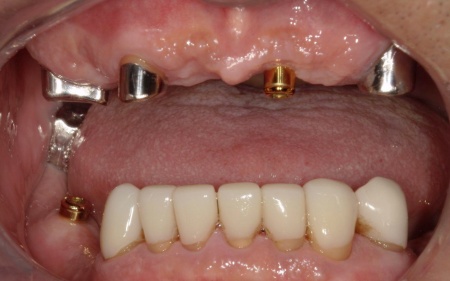

次に、上下左右の奥歯部に1本ずつ、左上前歯に1本、計5本のインプラントを埋入する手術を行いました。

続いて、残存している上の歯に対しては根管治療を行いました。

根管内の感染源を慎重に除去したうえで、再感染を防いで歯を長く使用するために、薬剤でしっかりと密閉しています。

ただ、右上前歯(犬歯)は状態が十分に改善せず、温存が困難であると判断したため、抜歯を行いました。

根管治療が終了した上の歯には、オーバーデンチャーの支えとなる内冠(入れ歯を安定させるための土台)を、インプラント部分にはロケーター(義歯をしっかり固定するための連結装置)を装着しました。

この仕組みにより、必要に応じて入れ歯の取り外しを可能にしながら、日常生活では安定した状態を保つことができます。